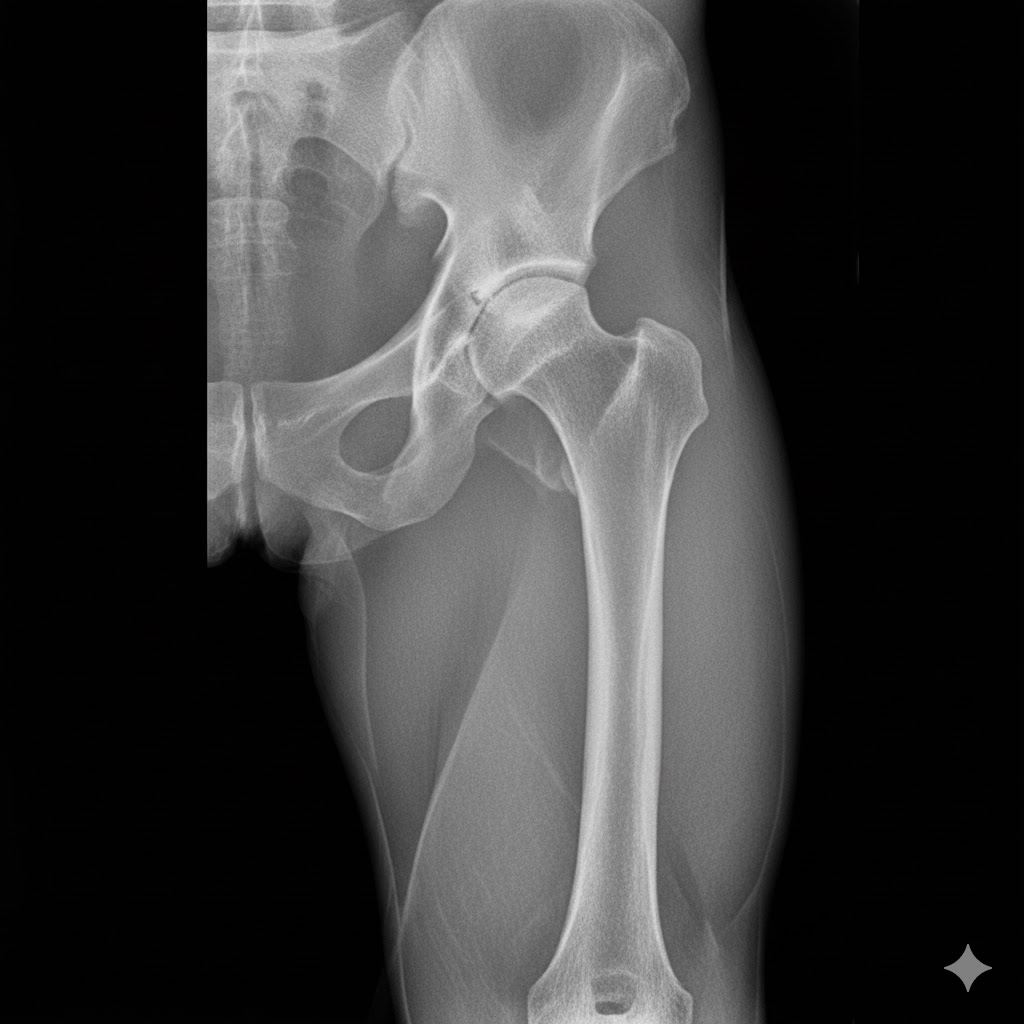

- تعویض مفصل لگن در موارد شدید و پیشرفته آرتروز لگن

- تشخیص و درمان دررفتگی مادرزادی لگن